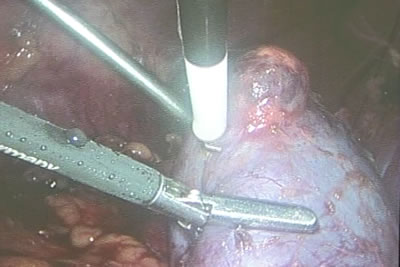

Углубляя мнополярную коагуляцию, проводится рассечение

тканей почки.

Этап резекции почки.

Этап резекции почки.

Резецируется "дно" опухоли.

Обновременно с резекцией проводится и коагуляция резекционной

поверхности.